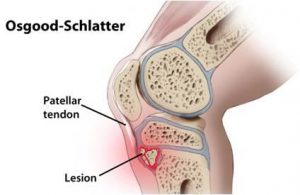

What a funny name for an injury! But what is it?

What a funny name for an injury! But what is it?